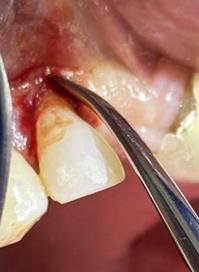

Figura 8. Irrigación del alveolo con solución fisiológica y sutura simple en la mitad del alveolo.

Elaboración: Los autores.